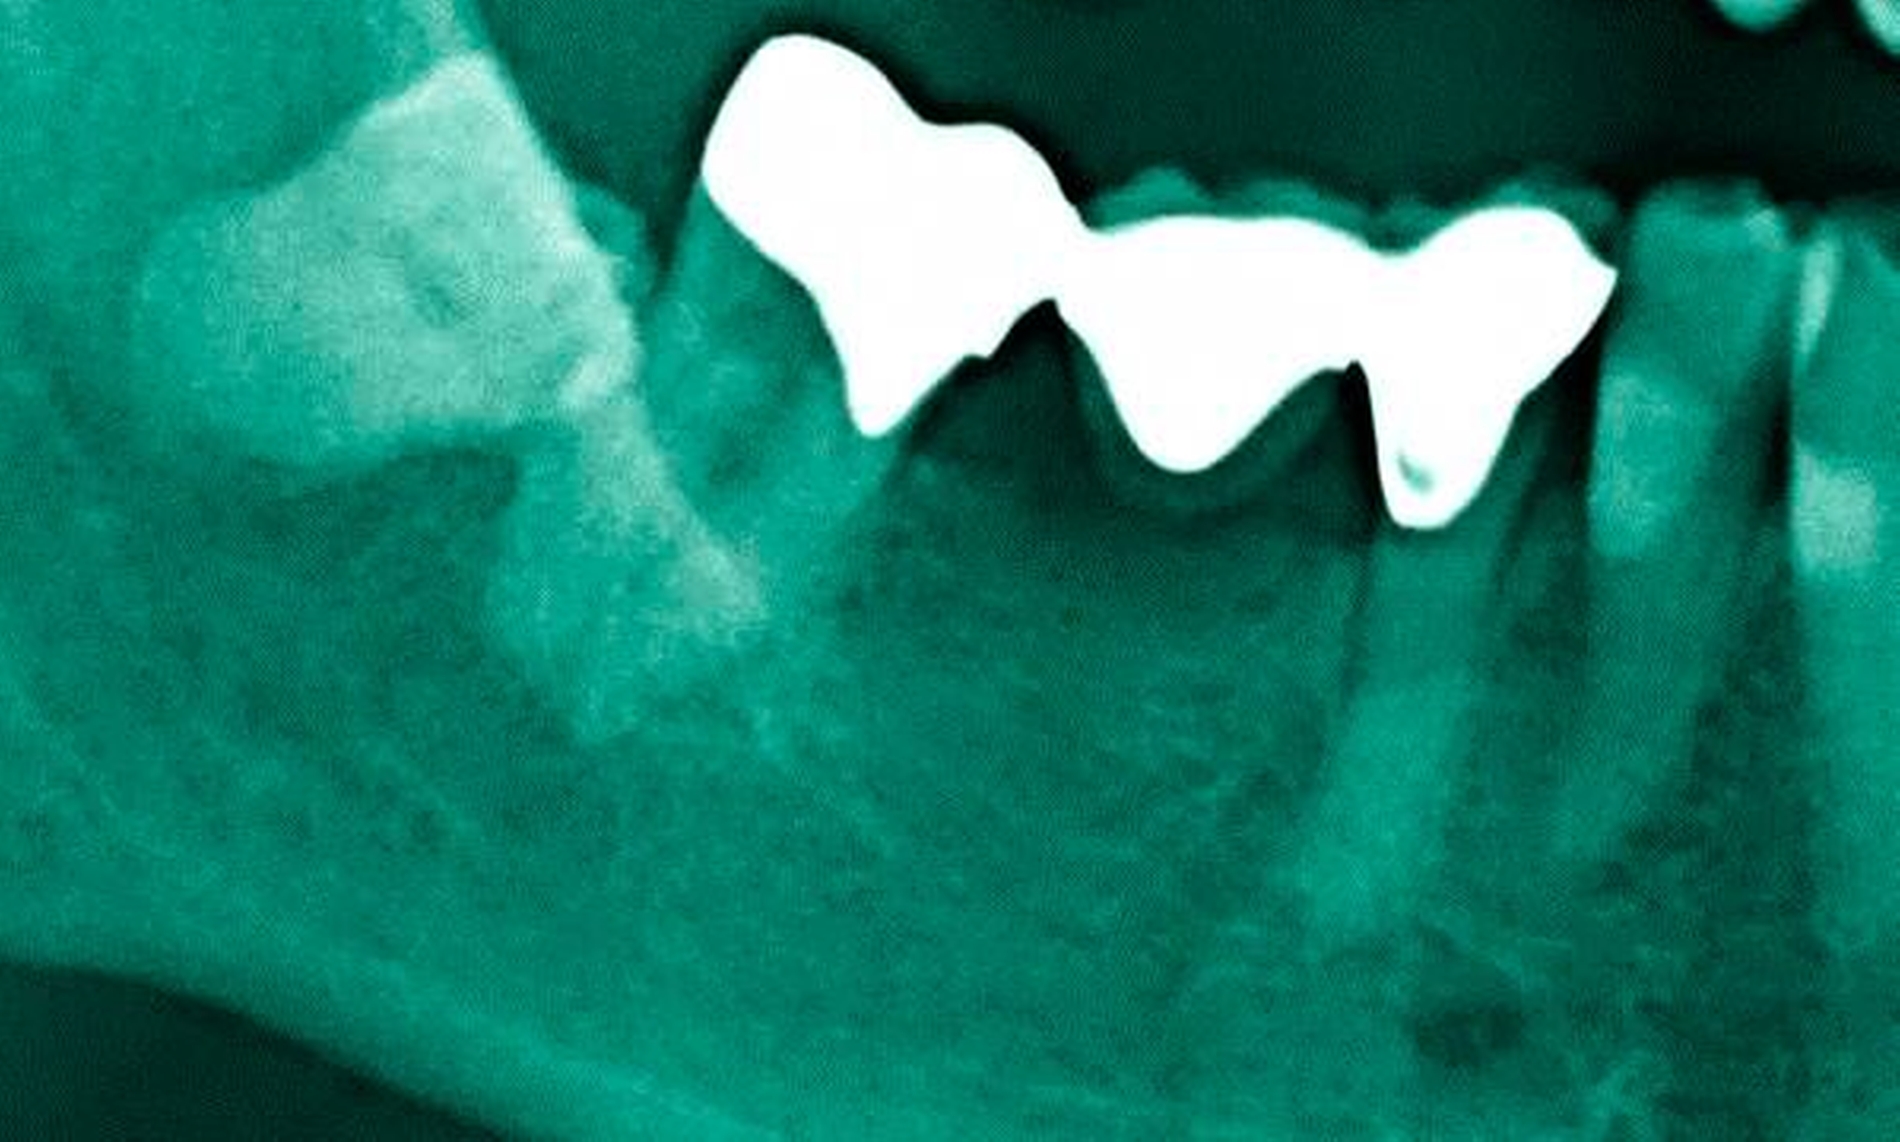

Abbildung 3: ausgedehnte Kronen- und Wurzelkaries unter einer Krone am Pfeilerzahn 47 einer seit Jahrzehnten eingegliederten Brücke von 45–47 bei einer 71-jährigen Patientin, die nach einer zerebrovaskulären Erkrankung unter Antikoagulantientherapie steht, vor etwa zwei Jahren hat sie eine Umstellung auf eine fluoridfreie Zahnpaste vorgenommen.